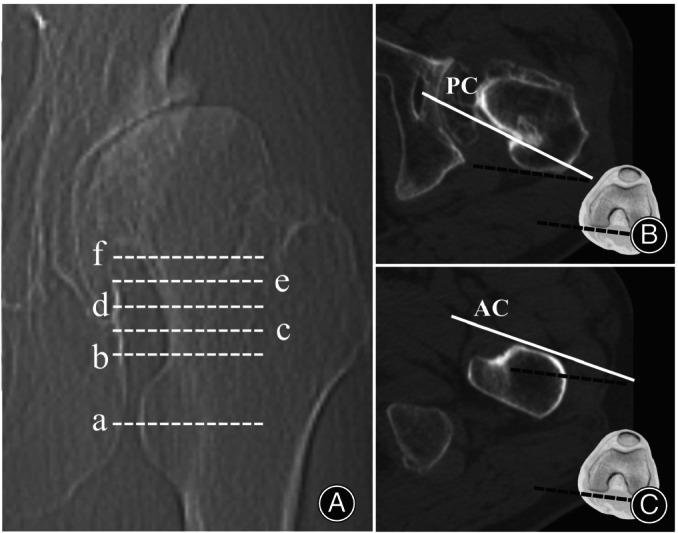

From January 2017 to December 2018, a total of 133 DDH hips that underwent THA were retrospectively analyzed. There were 76 Crowe type I, 27 type II, and 30 type III hips. The single-wedge stem was used in 49 hips, and the double-wedge stem was used in 84 hips. Preoperative native femoral anteversion at the femoral head-neck junction, anterior cortex anteversion at 2 levels of the lesser trochanter, posterior cortex anteversion at 5 levels of the femoral neck, and postoperative stem anteversion were measured using two-dimensional computed tomography. Predictive anteversion by the new method was calculated as the average anteversion formed by the anterior cortex at the lesser trochanter and the posterior cortex at the femoral neck.

For hips with different neck heights, different Crowe types, different stem types, or different femoral anteversions, native femoral anteversion showed widely varied differences and correlations with stem anteversion, with differences ranging from -1.27 ± 8.33° to -13.67 ± 9.47° and correlations ranging from 0.122 (p = 0.705, no correlation) to 0.813. Predictive anteversion formed by the anterior cortex at the lesser trochanter proximal base and posterior cortex 10 mm above the lesser trochanter proximal base showed no significant difference with stem anteversion, with less varied differences (0.92 ± 7.52°) and good to excellent correlations (r = 0.826).

Adopting our new method, predictive anteversion, measured as the average anteversion of the anterior cortex at the lesser trochanter proximal base and posterior cortex 10 mm above the lesser trochanter proximal base, predicted postoperative stem anteversion more reliably than native femoral anteversion.